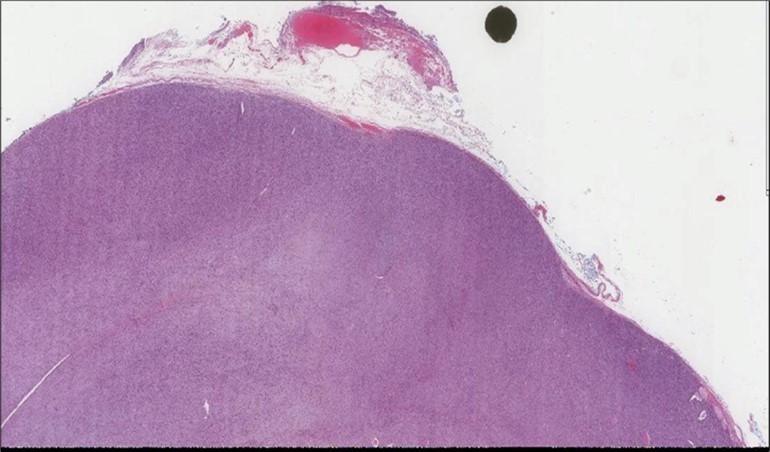

When diagnosing thyroid swelling, imaging studies have been helpful in differentiating malignant from benign tumors with US being used as an initial evaluation tool when assessing thyroid nodules. Tumors are categorized based on composition, echogenicity, shape, margin and echogenic foci into added scores determined by the TI-RADS system, which determines the need for FNA 13. Other imaging modalities include MRI and CT. However; radiological assessment does not distinguish between the types of thyroid cancer, and therefore FNA and biopsy are of crucial importance 3, 6. On a pathologic sample, LMS appears as spindled eosinophilic cells with elongated blunt-ended or cigar-like nuclei arranged in fascicles 2, 7 (Figure 1, Figure 2, Figure 3). Despite the unique microscopic morphology, LMS cannot be distinguished from other spindle cell tumors such as spindle cell variant of medullary thyroid cancer, anaplastic thyroid

Figure 1.Left thyroid Low power of the thyroid gland showing complete replacement of the thyroid by the neoplastic cells (H&E, ×4).

cancer, or other metastatic tumors without further testing with genetic or molecular studies 3, 7. Immunohistochemical testing plays a vital role in differentiating LMS from such similar tumors as it stains positive for vimentin and smooth muscle actin (SMA), and is variably positive for HHF35, desmin (50%-100%), and H-caldesmon 3, 6. Moreover, there were no reported cases where thyroid LMS stained positive for thyroglobulin, cytokeratin, calcitonin, chromogranin, or protein S100 3. Our patient’s left thyroid biopsy showed the characteristic microscopic features and was positive for SMA, desmin, caldesmon, P63 with patchy EMA (Figure 1, Figure 2, Figure 3, Figure 4) as well as her liver biopsy (Figure 5, Figure 6, Figure 7); whereas her right thyroid showed clear papillary thyroid cancer cell features (Figure 8, Figure 9).